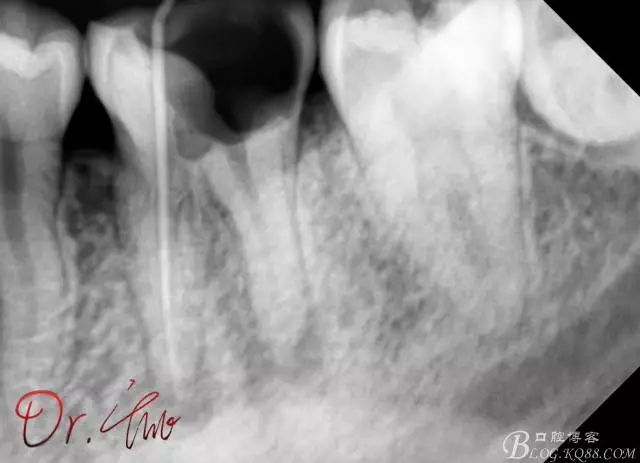

先來第一個病例

初診照

640.webp.jpg